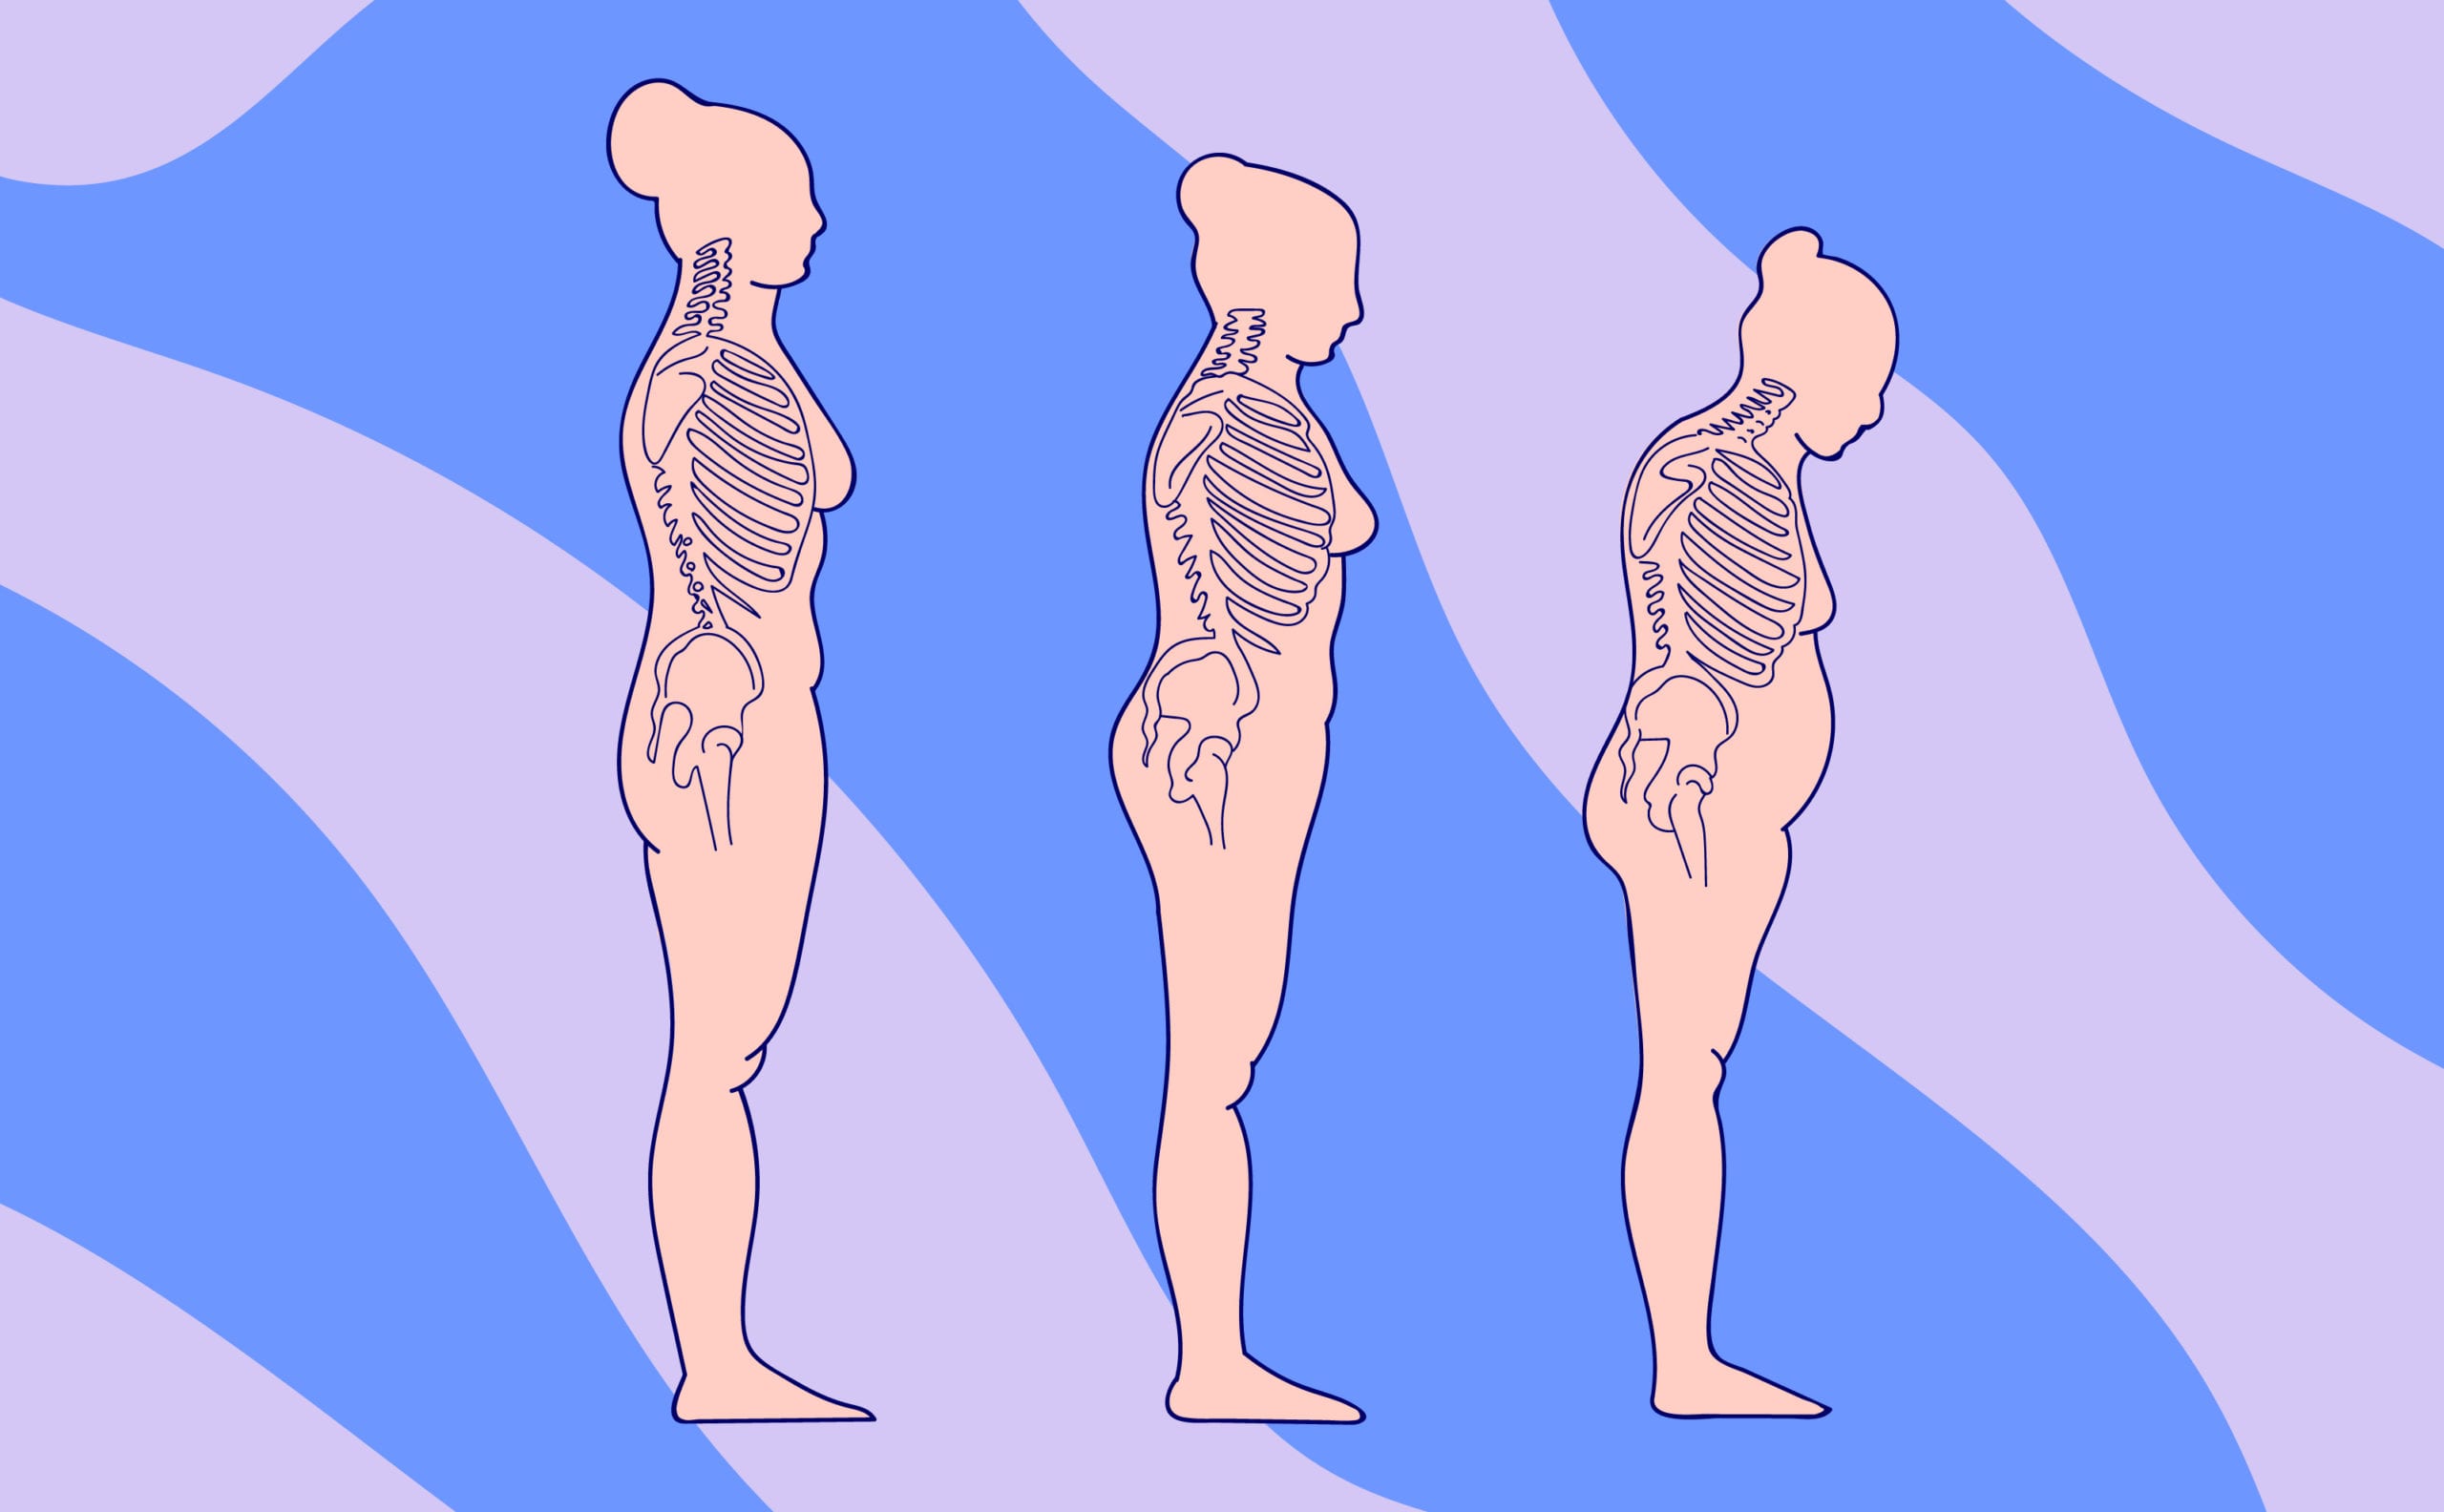

Declining estrogen affects our bone health, putting us at a greater risk for osteoporosis and periodontitis (inflammation of the tissues surrounding the teeth). It can also lead to bone loss in the jaw, which in turn exposes more of a tooth and leads to decay or tooth loss. Not-so-fun fact: osteoporosis makes us three times more likely to experience tooth loss, so it’s definitely important to talk to your healthcare provider (or Elektra!).